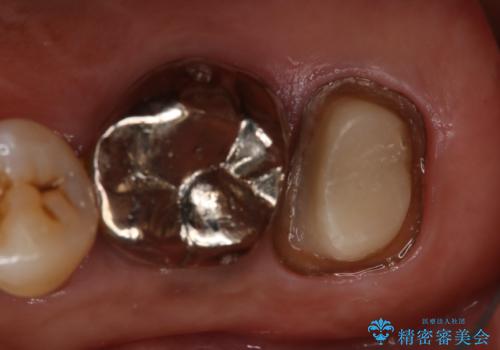

- 右上大臼歯の被せ物が取れたので作り直しを希望された患者様です。

被せ物は白くしたいとのことだったのでフルジルコニアクラウンでの治療を選択しました。

根管治療も必要だったので金属の土台を除去し、新しく土台を立て直した上で被せ物を装着しています。